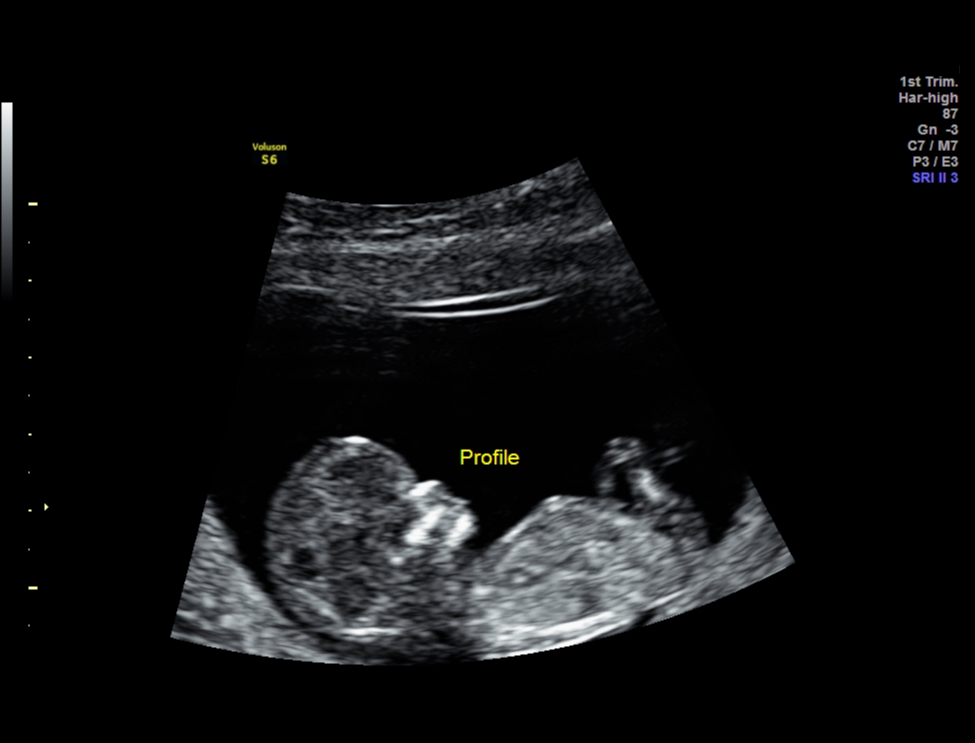

NUB , skull and potty shots at 12 weeks 1 day!! PLEASE HELP!

HI everyone, This is my 1st post in this forum after reading many threads about gender predictions and some of you ladies are very knowledgable. These are my NT scan pics for today.

One picture I asked tech what the gender is and she said she was very unsure but it might develop to girl part. What do you guys think? I googled some boys potty shot also has three lines and why mine is protruding ???

I am very confused